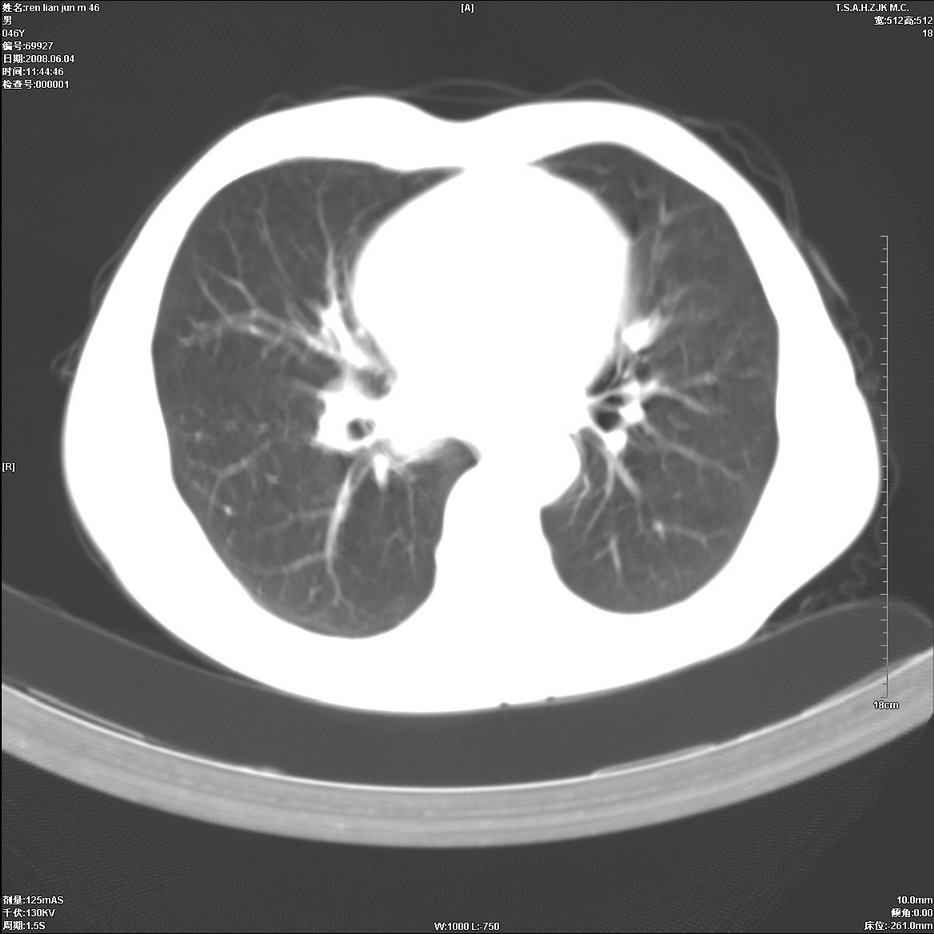

以下是引用qiu999在2008-6-5 17:14:00的发言:[br]考虑右肺中心型肺癌.颅内应做增强检查.

以下是引用形影不离在2008-6-5 19:18:00的发言:[br]右肺中心型肺癌并纵隔及左侧腋窝淋巴结转移,颅内应做增强检查。

以下是引用杀毒软件在2008-6-5 18:33:00的发言:[br]支持考虑右肺中心型肺癌,颅内病变是不是转移,不好说